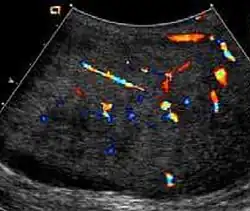

At ultrasound, the findings of acute epididymitis include an enlarged hypoechoic or hyperechoic (presumably secondary to hemorrhage) epididymis [Fig. 20a]. Other signs of inflammation such as increased vascularity, reactive hydrocele, pyocele and scrotal wall thickening may also be present. Testicular involvement is confirmed by the presence of testicular enlargement and an inhomogeneous echotexture. Hypervascularity on color Doppler images [Fig. 20b] is a well-established diagnostic criterion and may be the only imaging finding of epididymo-orchitis in some men.

-

Doppler ultrasound of epididymitis, seen as a substantial increase in blood flow in the left epididymis (top image), while it is normal in the right (bottom image). The thickness of the epididymis (between yellow crosses) is only slightly increased (7 mm). -

Doppler ultrasound of the scrotum of the same case, in the axial plane, showing orchitis (as part of epididymo-orchitis) as hypoechogenic and slightly heterogenic left testicular tissue (right in image), with an increased blood flow. There is also swelling of peritesticular tissue.